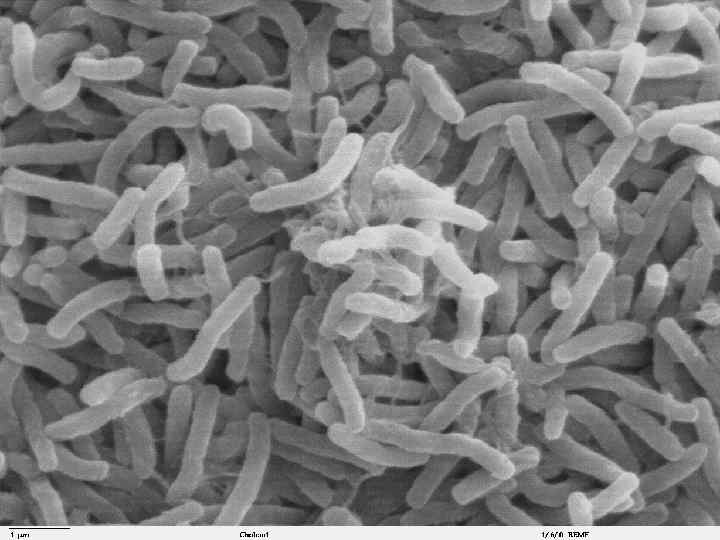

Vibrio cholerae

Vibrio cholerae